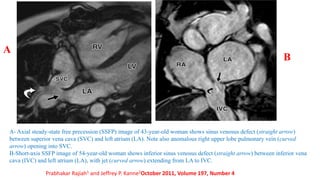

A- Axial steady-state free precession (SSFP) image of 43-year-old woman shows sinus venosus defect (straight arrow)

between superior vena cava (SVC) and left atrium (LA). Note also anomalous right upper lobe pulmonary vein (curved

arrow) opening into SVC.

B-Short-axis SSFP image of 54-year-old woman shows inferior sinus venosus defect (straight arrow) between inferior vena

cava (IVC) and left atrium (LA), with jet (curved arrow) extending from LA to IVC.

Prabhakar Rajiah1 and Jeffrey P. Kanne2October 2011, Volume 197, Number 4